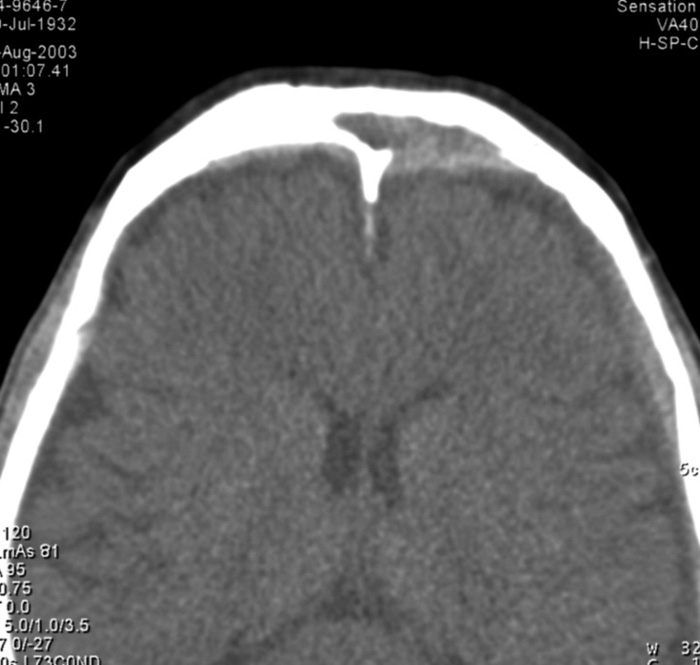

症例6:71歳男性

1993年、右蝶形骨洞嚢胞による圧排に伴う視力低下あり。嚢胞開放術施行。

1996年、蝶形骨洞嚢胞再発により再手術。

2ヶ月前(2003. 6)より右視力低下、視野障害及び頭痛出現。蝶形骨洞嚢胞再々発が疑われ、当院耳鼻科受診。

蝶形骨洞腔は鼻腔との交通あり、嚢胞再発は否定的。

図2